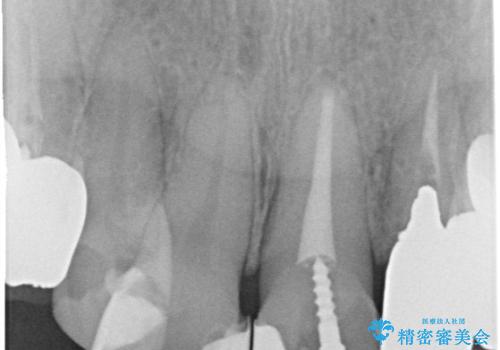

- 全体的な治療と、見た目をきれいにしたとのご希望で来院されました。

上顎の前歯はガタガタがあり、過去に治療した歯はつぎはぎのようになっており、審美的に周囲と調和がとれていない状態でした。

治療計画としては

①仮歯を装着

②矯正治療

③セラミック装着

の順で行いました。